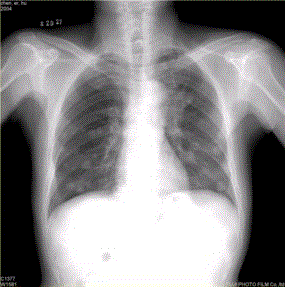

问题 患者男,45岁,因肝硬化、肝癌行肝移植术后6个月,咳嗽2周,来院复查。CR及CT影像如下图。 对于转移瘤和原发癌的关系,描述正确的有

选项 A.肺内转移最多的原发瘤为肝癌 B.原发支气管肺癌可转移到同侧和对侧 C.乳腺癌肺转移可通过血行和淋巴途径,还可经胸膜播散 D.睾丸精原细胞瘤的肺和淋巴结转移灶密度较低 E.中枢神经系统肿瘤易发生肺内转移 F.脑转移瘤中最常见的原发肿瘤为肺癌

答案 BCDE

解析 BCDE